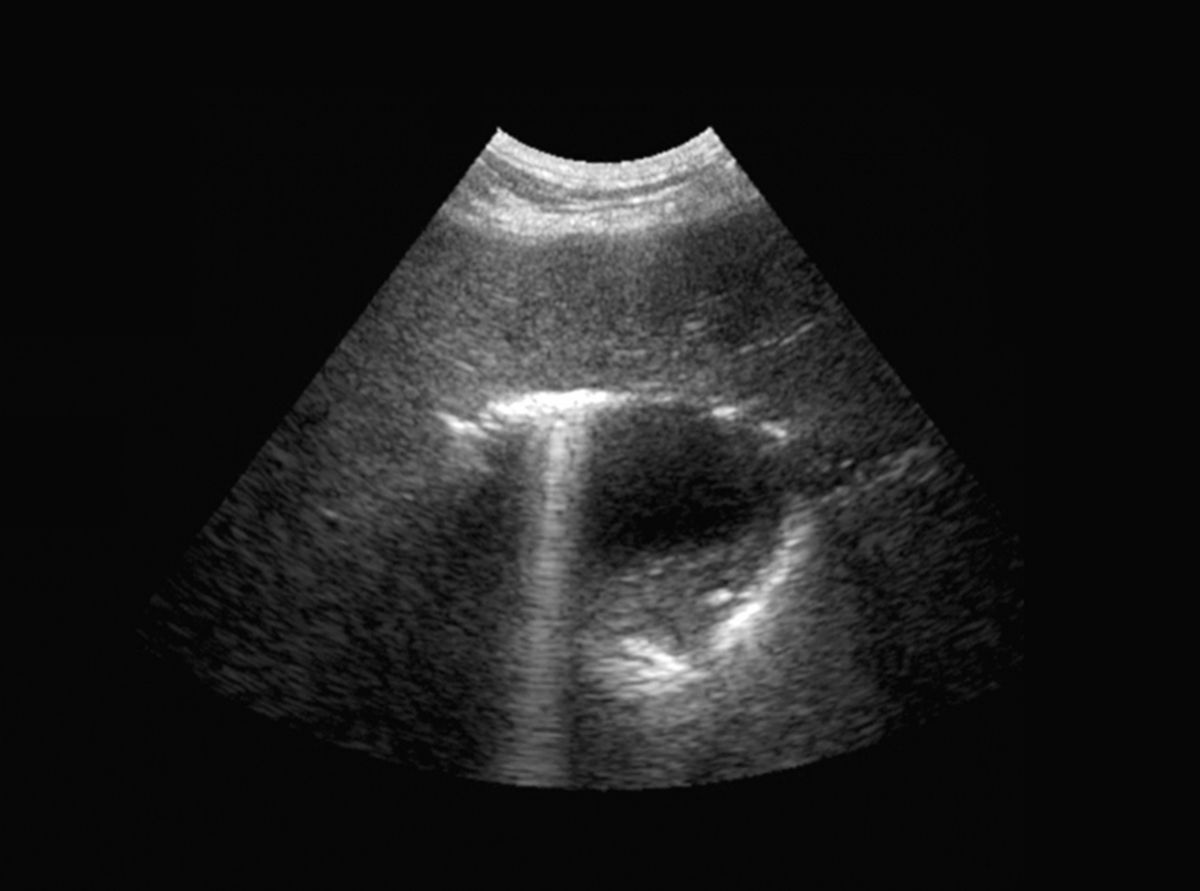

Radiografia poate contribui la evaluarea dimensiunii, formei, poziției, opacității și marginilor ficatului, precum și la detectarea prezenței gazelor sau a mineralizării (Figura 2). Ecografia contribuie la determinarea gradului de afectare hepatică (focală, multifocală sau difuză), precum și la evaluarea vascularizației și poate facilita prelevarea de probe (pentru citologie, cultură și biopsie) (Figura 3). Rețineți că absența modificărilor ecografice nu înseamnă neapărat că ficatul este sănătos.

Ecografie abdominală a unui câine care prezintă gaz în vezica biliară din cauza colangitei emfizematoase.

Figura 3. Ecografie abdominală a unui câine care prezintă gaz în vezica biliară din cauza colangitei emfizematoase.© Jordi Puig